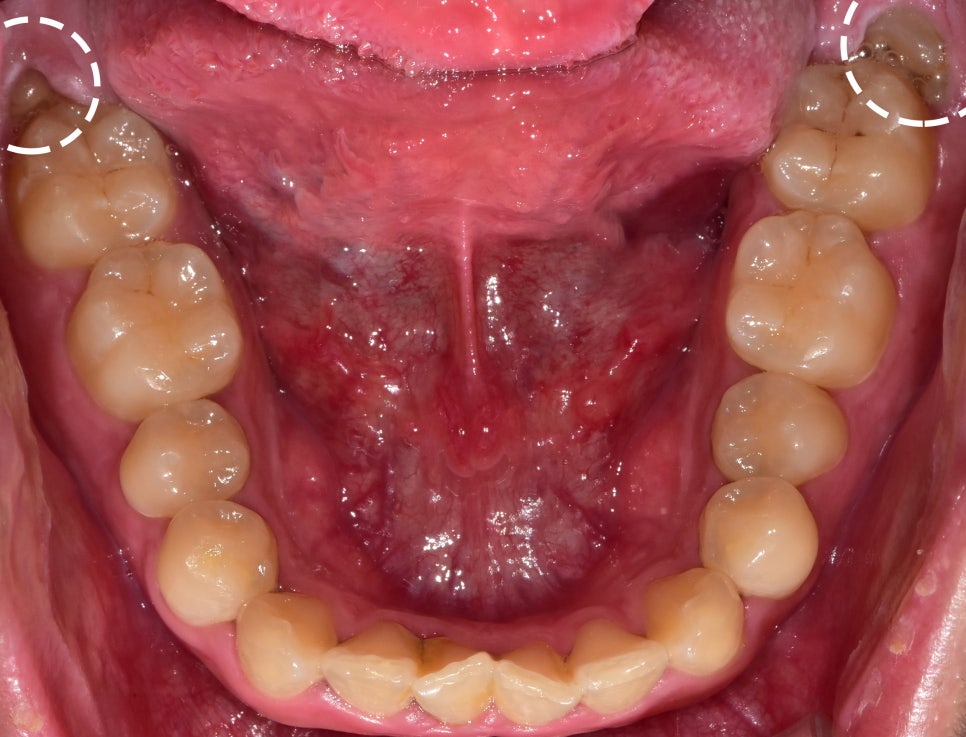

아울러, 사진에서 볼 수 있는 것 처럼

치아의 치관이 조금이라도 맹출이 되어있다면

미리미리 발치를 하는 것 또한 도움이 될 수 있습니다.

예방 차원에서요^^

사진으로 보면,

좌측 및 우측을 동시에 뽑은것처럼 보여지는데…

환자께서도 식사를 하셔야겠죠?

한쪽을 먼저 뽑은 뒤에,

한달뒤에 남은 쪽을 뽑아드렸습니다^^